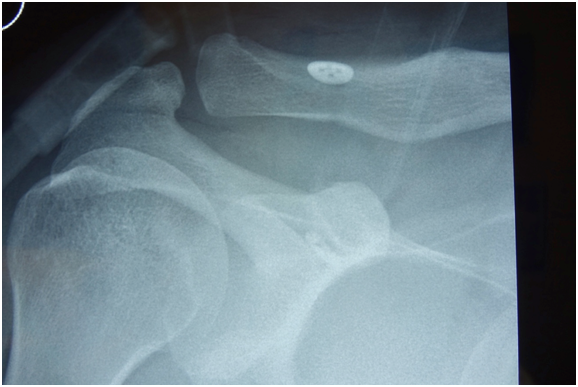

At final follow-up, no patient displaced to the preoperative state. Thirteen (52%) patients displaced to a grade II level (Rockwood classification3). These patients averaged 10 days (4-16 days) from the date of injury to the date of surgery. (Figure 3 & Table 1) Eight (32%) of the 25 had displaced back to a grade III level (Rockwood classification3). These patients averaged 18 days (6-38 days) from the date of injury until date of surgery (Figure 4 & Table 1).

Figure 3 Grade II loss of reduction, 24 weeks after surgery.